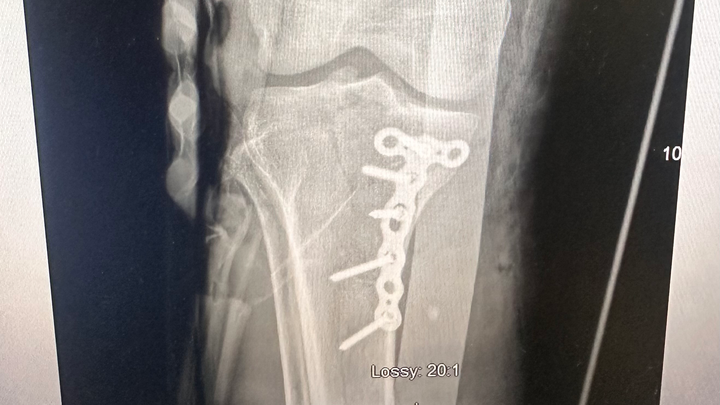

Hello, my name is Dream Smith, and I need urgent help to walk again. Four months ago, I suffered a traumatic leg injury that completely changed my life. I fractured my tibia and tore my ACL - both requiring surgery. I had my first surgery to repair the fracture with permanent rods and screws. But I was told immediately that I would also need ACL reconstructive surgery, or else I could become permanently disabled.